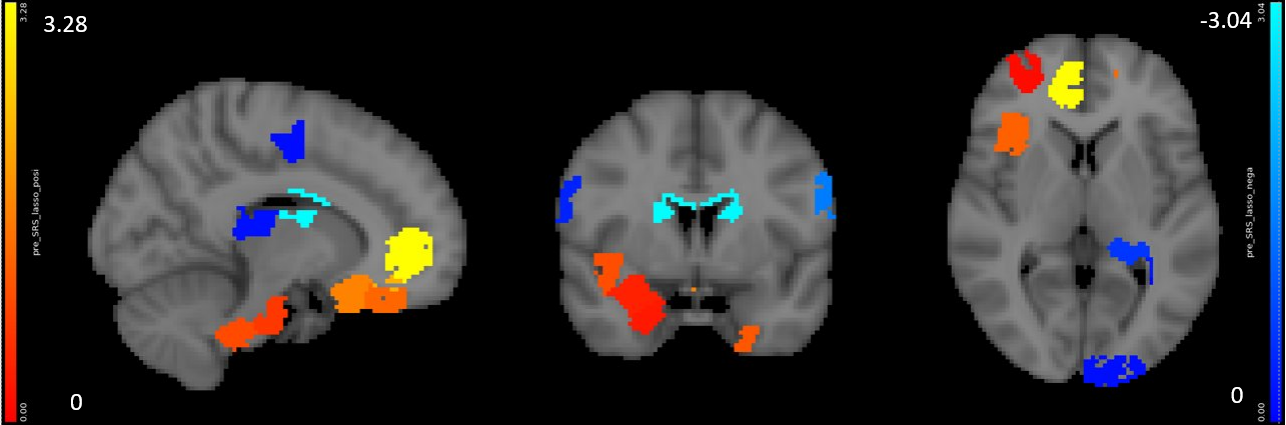

(a) Region-level elastic net model for pre-treatment SRS

For SRS scores, we found no predictive models in the literature. Kaiser et al. reported regions of correlation r=0.502 [11] in analytical modeling, while our predictive model achieved r=0.45 (Fig. 6(a)).

Neurosynth decoder results (Fig. 9(d), Fig. 10 right figure) show that selected regions match the literature [11]. The selected regions are slightly different across experiments due to different tasks, datasets and target measures. Many regions are shared across experiments, such as prefrontal cortex and visual cortex.